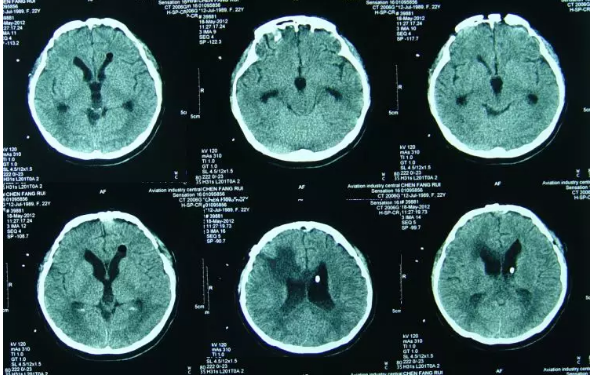

查头颅CT:脑室扩张,左侧侧脑室外引流术后状态(图-6)。

图-6:2012年5月4日头CT